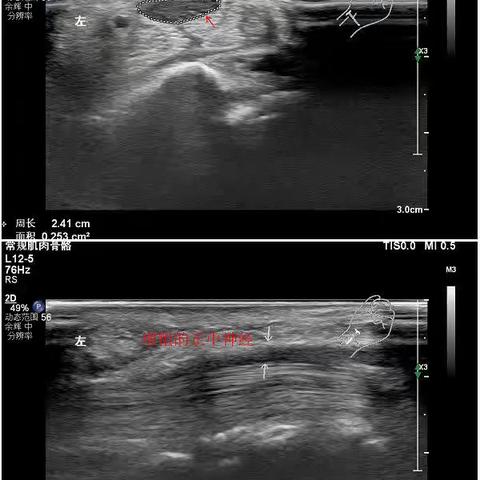

肌骨超声知多少?---我院超声科开展肌骨超声纪实